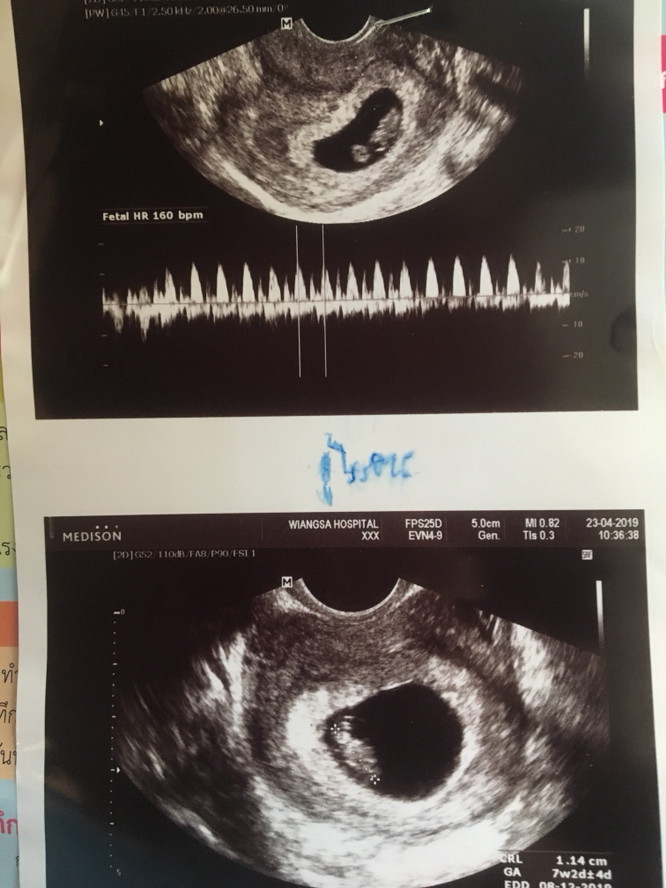

ตอน7วีคกับ2วันค่ะ ตอนนี้15วีคแล้ว💗

เห็นตอน7วีคค้าาา เห็นหัวใจเต้นแย้ววว😍